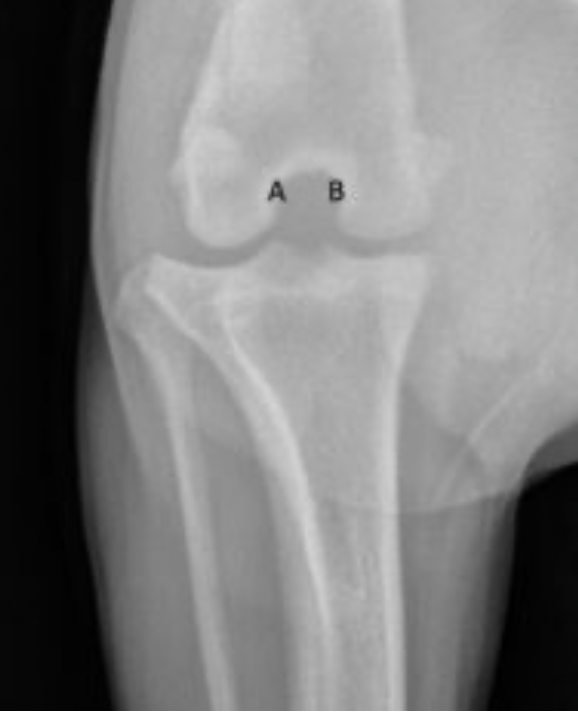

Q

Label the structures

A

A = patella

B = distal femur

C = fabellae

D = tibia

E = fibula